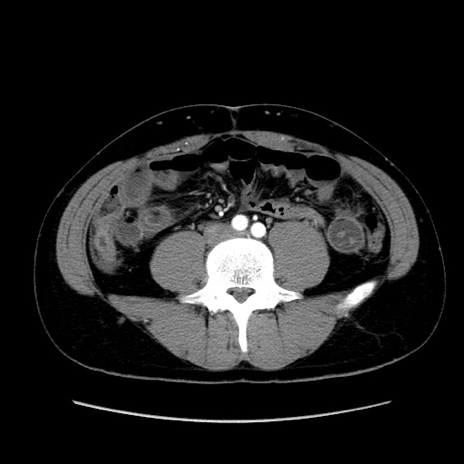

冠状断像

【症例】20歳代 男性

【主訴】心窩部痛

【現病歴】今朝より上腹部痛あり。一旦軽快していたが再度出現したため救急要請。昨日夕に白身の魚を含む刺身を食べた。

【身体所見】BP 136/89mmHg、HR 74/min、BT 37.0℃、腹部:膨満、軟、心窩部に圧痛あり。反跳痛なし、筋性防御なし、腸雑音やや亢進あり。

【データ】WBC 17700、CRP 0.48